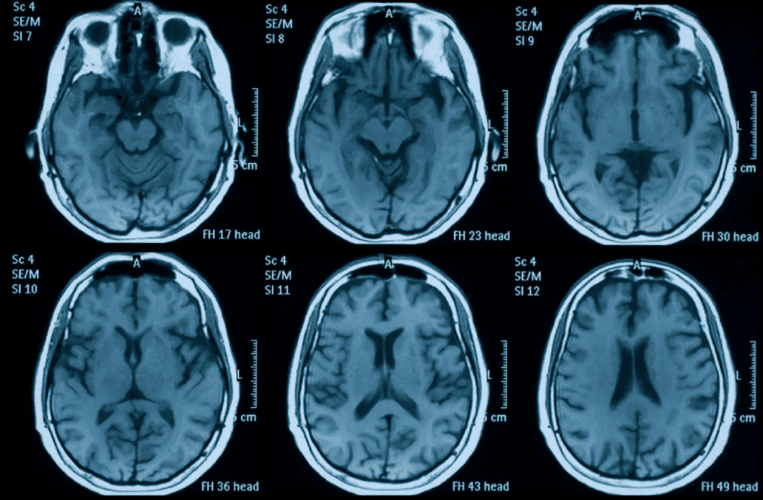

Studija sprovedena na Univerzitetu u Notingemu, koju je predvodio Ali-Reza Mohamadi-Nežad, pokazala je da su mozgovi učesnika „ostarili“ u proseku za 5,5 meseci, i to nezavisno od bilo kakvih infekcije. Uzrok bi mogao da bude hronični stres, osećaj usamljenosti, izolacija tokom karantina, ali i promene u načinu života – poput smanjenog kretanja ili povećane konzumacije alkohola.

Istraživači su koristili veštačku inteligenciju obučenu na preko 15.000 moždanih skenova, kako bi uočili strukturne promene koje dolaze sa starenjem. Zatim su analizirali dve grupe: kontrolnu grupu sa skenovima pre marta 2020, i eksperimentalnu grupu koja je imala jedan snimak pre, a drugi nakon početka „pandemije“.

Promene u sivoj i beloj masi mozga bile su prisutne i kod osoba koje nikada nisu imale bilo kakvih zdravstvenih problema, što sugeriše da je sama „pandemija“, kao društveni i psihološki fenomen, ostavila meren neurološki trag.